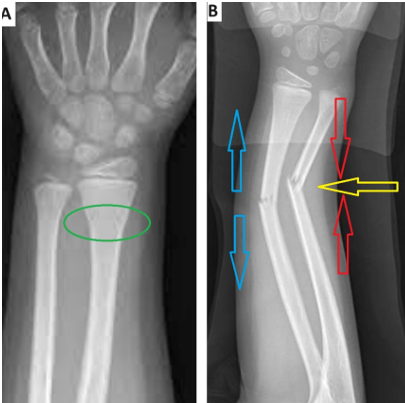

The term “torus” is derived from the Latin word “tori” and refers to the integrity of the periosteum in the metaphyseal-diaphyseal junction, implying undisturbed or minimally disturbed fractures with intact cortex [1]. It is believed that compression forces at the transitional zone between trabecular metaphyseal bone and lamellar dense diaphyseal bone in its pathophysiology[2]. Distal radius torus fractures (DRTF) are common fractures in childhood and constitute a significant portion of the orthopedic workload in emergency departments [1, 3, 4]. They typically occur after a fall while the wrist is in extension position, and patients present with a history of tenderness and swelling. Torus fractures and greenstick fractures are specific to the pediatric patient population[5, 6]. As seen in Figure 2, torus fractures are more stable compared to greenstick fractures [7]. Torus fractures can usually be successfully treated with conservative methods; however, minimally displaced fractures are of concern due to their potential instability[8]. There are significant differences in the treatment of DRTF among different hospitals and orthopedic surgeons. The standard treatment involves immobilization in a short-arm cast for three weeks followed by outpatient examination and control radiography for cast removal [2, 9]. Alternative treatments such as orthoses, elastic bandaging, and circular plaster immobilization have been described. Recent studies have shown that circular plaster immobilization may be unnecessary and that short-term wrist support may be sufficient [2]. Our hypothesis is that treatment with a static wrist splint may be sufficient for torus fractures and that using a wrist splint that can be removed and re-applied after necessary precautions, instead of methods like circular plaster that may disrupt patient comfort, may be advantageous. Therefore, in our study, we attempted to determine the treatment outcomes, both in terms of pain and function, of patients with DRTF treated with a static wrist splint.

Figure 2. A illustrates a torus fracture (buckle fracture), showing the swelling and plastic deformation at the metaphyseal- diaphyseal junction indicated by the green circle. FB depicts a greenstick fracture, where the deforming force, compressive forces indicated by the red arrow, and tensile forces represented by the blue arrow are shown. In greenstick fractures, there is plastic deformation on one side while the opposite cortex has a fracture